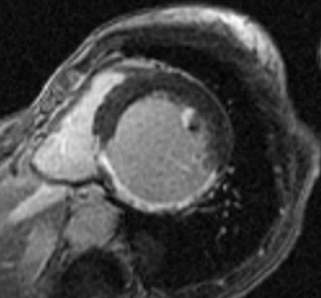

Fig.1., 2.: Hypertrophic obstructive cardiomyopathy: Longitudinal and short axis slices of delayed enhancement of contrast material in the heart: pathologic enhancement is visible in the myocardium in the asymmetrically thickened left ventricular wall, referring to a degenerative-fibrotic process.

In case of dilated cardiomyopathy, the enlargement occurs in the ventricles. The wall becomes thinner and the pump function becomes impaired, leading to the decrease of ejection fraction. Most commonly it is caused by coronary diseases, but metabolic diseases, inflammatory processes and toxic damage can also be a cause. The cardiac morphology and function are well assessable with echocardiography, while MRI can play a role in the differential diagnostics.